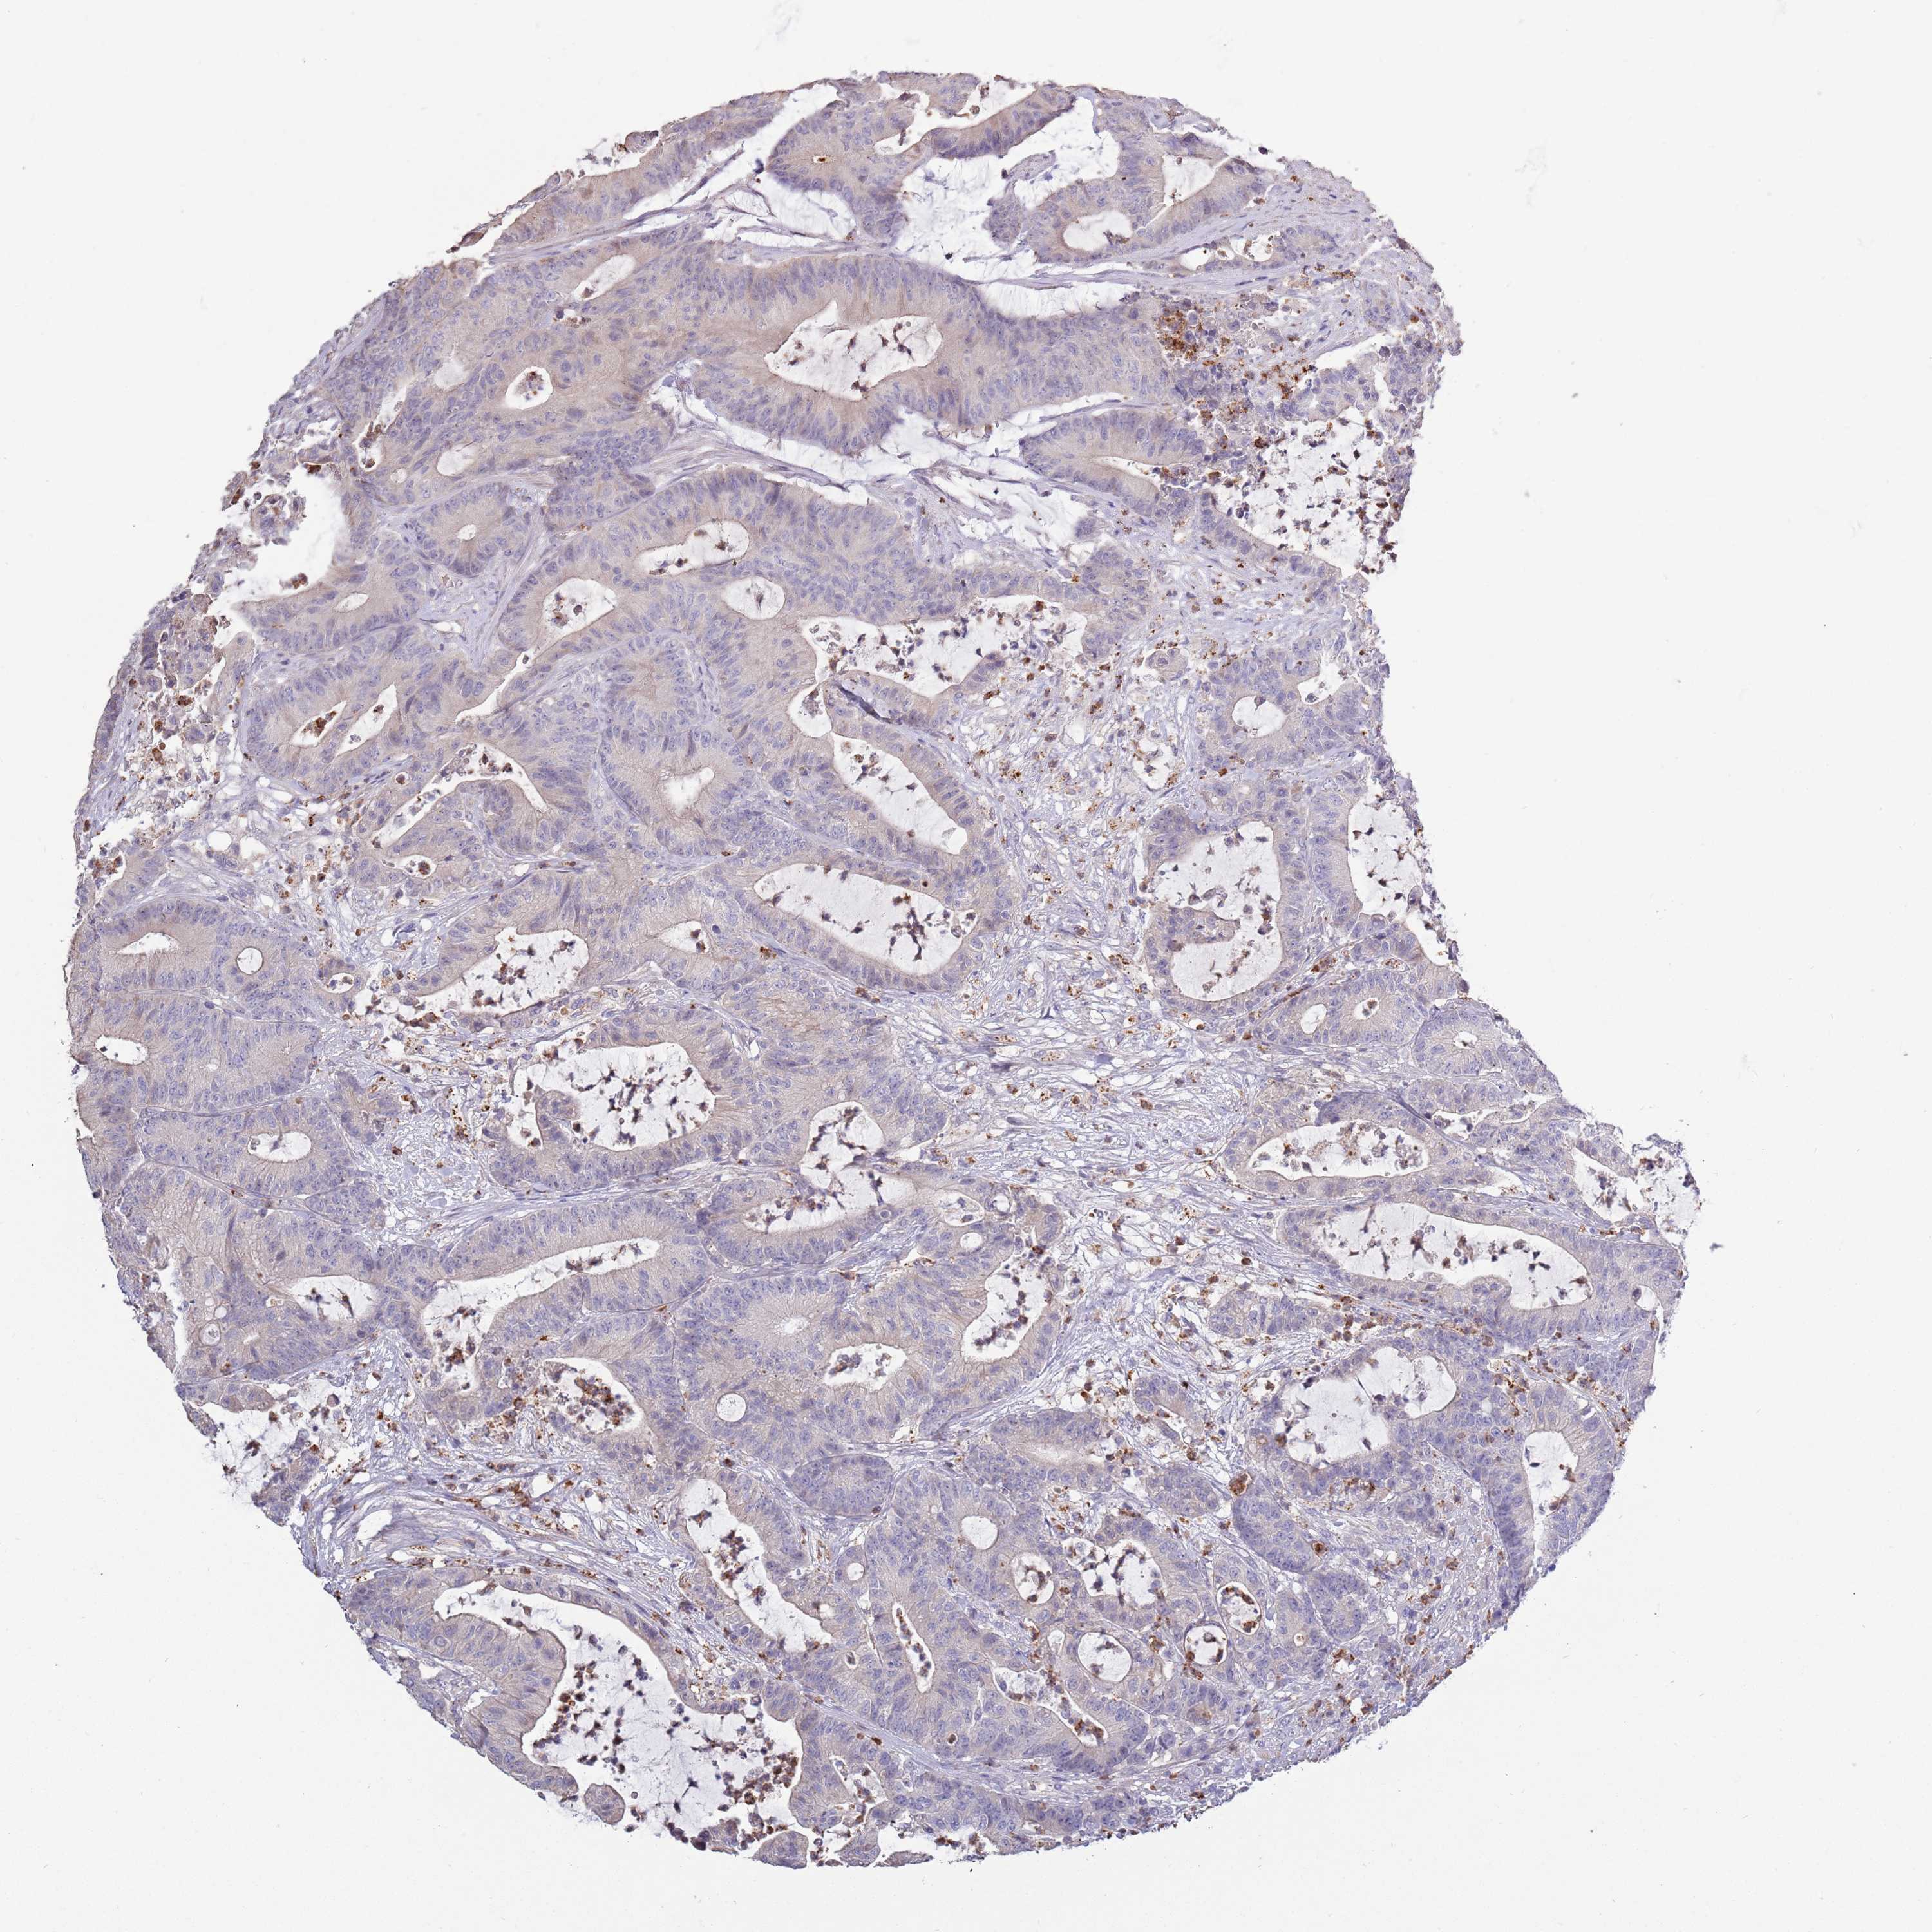

CANCER COLORECTAL CANCER Show tissue menu

Colorectal cancer

Rectum adenocarcinoma